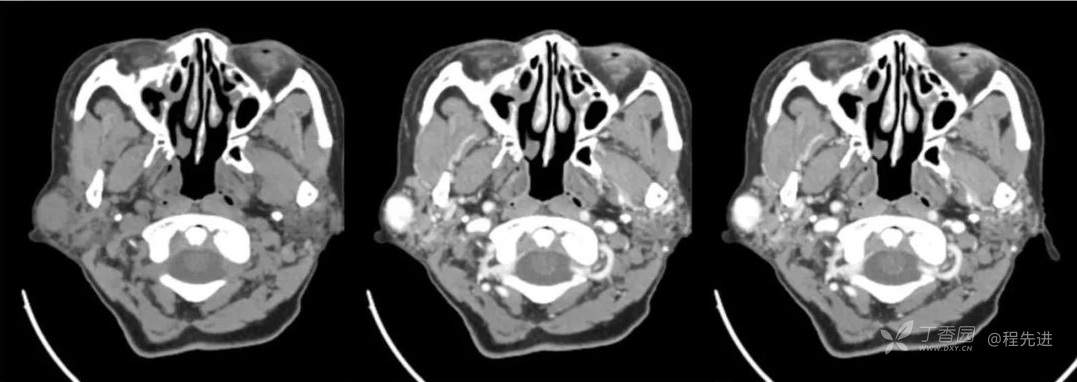

红五月特别精彩病例|发现右侧耳下肿物12年,罕见典型病例,见过就可以秒【病理公布】

简要病史:发现右侧耳下肿物12年,不痛,缓慢生长

既往史:19年前因右侧腮腺肿物在当地医院行手术(具体不详),17年前因右侧腮腺肿物复发再次在当地医院手术(具体不详)

体格检查:右侧耳下可扪及大小约3*3cm肿物,质地中,边界清,活动可,无明显压痛。颈部未扪及明显肿大淋巴结